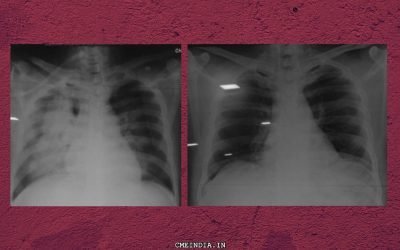

Right Lung Massive Opacity, SOB, Pyrexia and Raised Count: What could it be?

CME INDIA Case Presentation by Dr Deepak Gupta, DM, Card, Pulse Hospital, Ranchi. CME INDIA Case Study: Case presented in CSI, Jharkhand and CME INDIA groups In this COVID era, Severe SOB. Fever, high count. Patient presented with chest pain on 30th October, 2020....